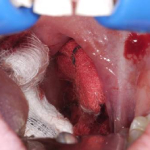

2) Post-Tonsillectomy Hemorrhage: A Three-Pronged Approach

Our second most-read article (6,080 views) was an approach to a condition most emergency physicians would rather avoid, especially if you don’t have an ear, nose, and throat (ENT) physician in-house. This column by Anton Helman, MD, on post-tonsillectomy hemorrhage comes highly recommended. Make sure you have topical epinephrine, tranexamic acid, and maybe even desmopressin available in a pinch.